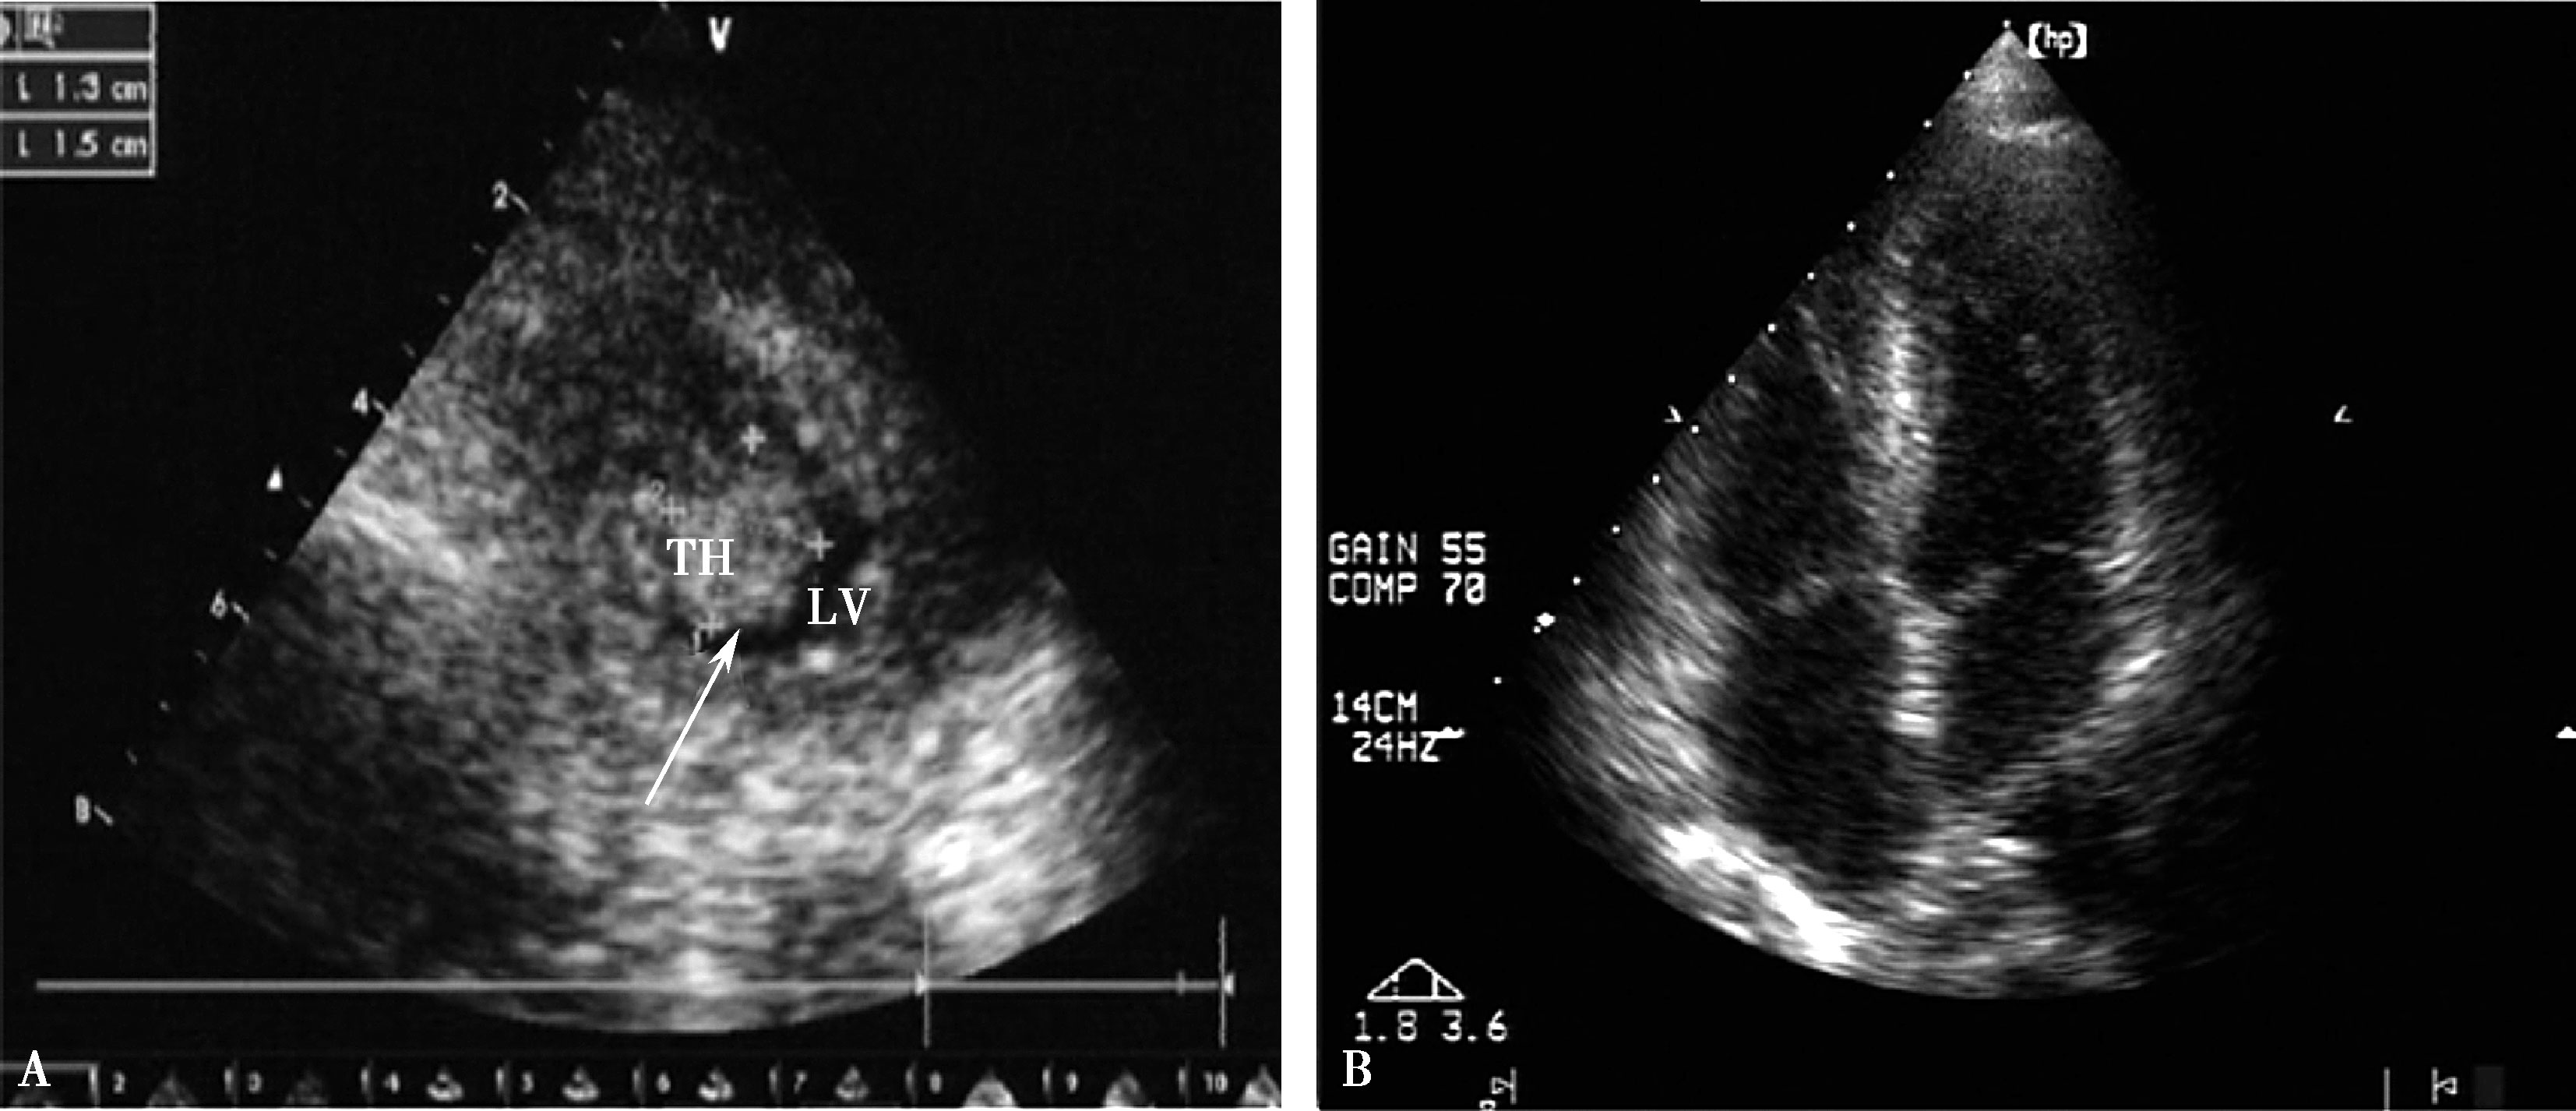

胸部CT:双肺多发斑片、结节影,以双肺上叶及下叶背段为主,多考虑肺结核;纵隔及肺门多发淋巴结肿大,部分钙化;左侧胸腔积液,双侧胸膜增厚(图10-1)。

图10-1 胸部CT

双肺多发斑片及结节影、纵隔及肺门淋巴结肿大,部分钙化